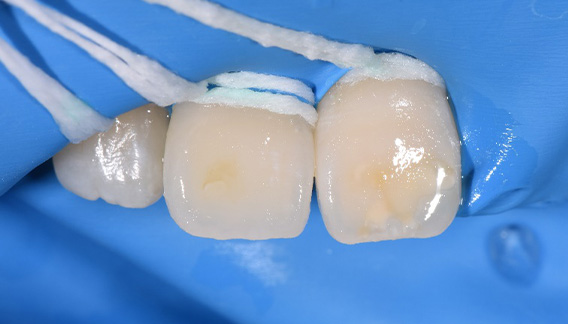

| 院長コメント | ①むし歯を治療して歯を型どりする時 ②ジルコニアを歯と接着させる時 唾液を極力排除する必要があります。ラバーダムというゴムの膜を用いて歯を唾液から隔離します。今回はかぶせ物(クラウン)の形で接着面全周をラバーダムの上に出すのはかなり難しかったのですが、工夫をすることで接着面全てをラバーダムの上に設置することができ、接着力を最大限に発揮できました。 |

| 院長コメント | 神経を抜いた歯をジルコニアクラウンで修復しました。ホワイトニングをされる予定だったので技工士・患者様と打ち合わせをして歯の色を2段階白く作成しました。しっかりと全周ラバーダムの上にだして唾液から隔離した状態で接着技術を最大限に発揮させています。 |

| 院長コメント | 歯と色がマッチしやすいセラミックを採用しました。ジルコニアよりもよりグラデーションがついて色がなじみやすい材質となります。ラバーダムを用いることで接着力を最大限引き出すことができるようになり、むし歯の再発するリスクを極限まで下げることができます。 |